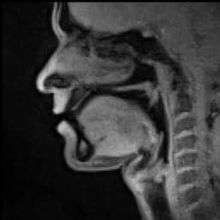

Normal human speech is produced with pressure from the lungs, which creates phonation in the glottis in the larynx, which is then modified by the vocal tract into different vowels and consonants. However humans can pronounce words without the use of the lungs and glottis in alaryngeal speech, of which there are three types: esophageal speech, pharyngeal speech and buccal speech (better known as Donald Duck talk).